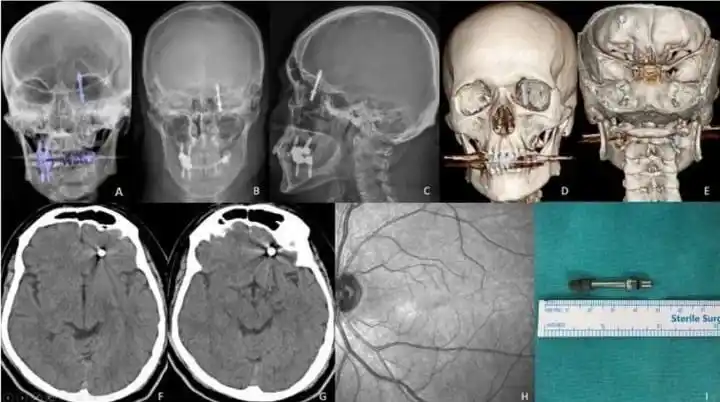

BURSA (İHA) – Bursa’da diş tedavisi için gittiği özel klinikte yaptırdığı implant işlemi, fabrika işçisi Ramazan Yılmaz’ın (40) hayatını kabusa çevirdi. İddiaya göre, doktorun hatalı müdahalesi sonucu implant vidası çene kemiğini delip kafatasına saplandı. Ölümle burun buruna gelen talihsiz adam, saatler süren ameliyatla hayata tutundu. Ancak aradan geçen 2 yıla rağmen ne adalet yerini buldu, ne de sorumlular cezalandırıldı. Hatalı bulunan diş hekimine ise sadece 10 muayene ücreti ceza verildi.

Nilüfer ilçesinde özel bir diş kliniğinde muayene olan Yılmaz’a, dişlerinin sallandığı gerekçesiyle implant tedavisi önerildi. Ancak iddiaya göre, doktor A.D.’nin hatalı müdahalesi sonucu implant vidası çene kemiğini delip kafatasına saplandı.

Baygınlık geçiren Yılmaz, kliniğin kendi aracıyla hastaneye kaldırıldı. Tomografi çekiminde vidanın beynine kadar ilerlediği ortaya çıktı. Acil ameliyata alınan talihsiz adam, saatler süren operasyonla ölümden döndü.